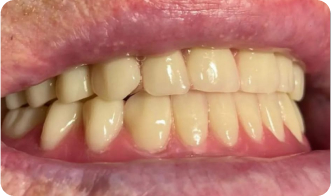

Установка All-on-4

До приёма:

• Полная адентия зубов

• Атрофия костной ткани

Результат:

• Установка имплантов Osstem

• Костная пластика

Срок: 2 дня